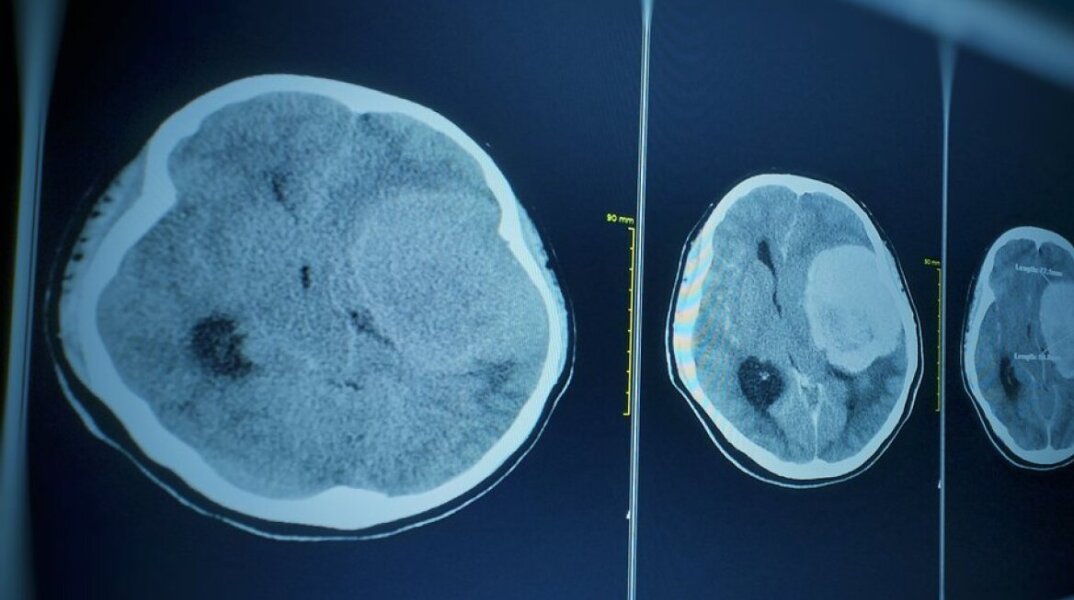

Ανήλικος στις ΗΠΑ πέθανε από αμοιβάδα που τρώει τον εγκέφαλο

Ένας ανήλικος έχασε τη ζωή του στη Νεβάδα εξαιτίας επιπλοκών μηνιγγοεγκεφαλίτιδας αφότου προσβλήθηκε από μια σπάνια αμοιβάδα η οποία «τρώει» τον εγκέφαλο, σύμφωνα με τις υγειονομικές αρχές της αμερικανικής πολιτείας.

Το θύμα, που περιγράφεται ως «κάτοικος της κομητείας Κλαρκ, ηλικίας κάτω των 18 ετών», εκτιμάται πως μολύνθηκε στη λίμνη Μιντ στις αρχές Οκτωβρίου και τα πρώτα συμπτώματα εκδηλώθηκαν μια εβδομάδα αργότερα.

Η αμοιβάδα Naegleria fowleri είναι ένας μονοκύτταρος οργανισμός, τόσο μικρός που είναι ορατός μόνο με μικροσκόπιο, αναφέρουν τα αμερικανικά Κέντρα Ελέγχου και Πρόληψης Νοσημάτων (CDC). Συναντάται συνήθως σε περιοχές με λιμνάζοντα ύδατα και σπανιότερα σε πισίνες με ανεπαρκή χλωρίωση ή σε μολυσμένο νερό της βρύσης.

Η νεγλαιρίαση – γνωστή επίσης ως πρωτογενής αμοιβαδική μηνιγγοεγκεφαλίτιδα (primary amoebic meningoencephalitis ή PAM) – είναι μια σπάνια λοίμωξη του εγκεφάλου. Τα συμπτώματα μπορεί να περιλαμβάνουν έντονο πονοκέφαλο, πυρετό, ναυτία και εμετό. Καθώς η λοίμωξη επιδεινώνεται, τα συμπτώματα – που εμφανίζονται 1-12 ημέρες μετά την έκθεση – μπορεί να εξελιχθούν σε επιληπτικές κρίσεις ή παραισθήσεις και να οδηγήσουν στον θάνατο.

Πέρυσι, ένα επτάχρονο αγόρι πέθανε από ναιγλερίαση στην Καλιφόρνια , αφότου μολύνθηκε – όπως εικάζεται – ενώ κολυμπούσε σε λίμνη στη Βόρεια Καρολίνα. Οι υγειονομικές αρχές της πολιτείας υπογράμμισαν τότε πως μόλις 10 κρούσματα PAM, για τα οποία ευθύνεται η αμοιβάδα Naegleria fowleri, είχαν αναφερθεί στην Καλιφόρνια από το 1971.